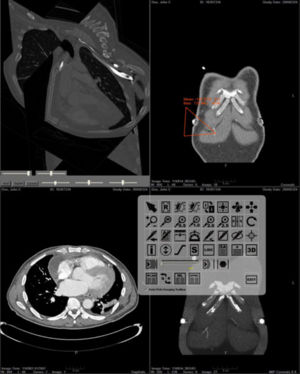

Background/Purpose: Dr. Pohl's research involves developing an automatic segmentation approach identifying major anatomical compartments from torso CT scans. Using 3D Slicer, he developed a procedure for automatically segmenting the body, bone structures, lungs, and hart from CT images (see figure). The method iterates between the identification of anatomical structures and the registration of an “atlas” to the CT data set of the subject. The atlas is based on CT data set, which we call template, and a label map that already identifies the structures of interest in the template. In the first iteration, the template with the segmentation of the body is mapped onto the CT data set of the subject. This results in a very accurate segmentation of the subject’s body. The method then combines the segmentation of the body and the CT images of the subject to identify the lungs and bone structures. In the second iteration, the method maps the atlas specific label map of body, bones, and lungs to the corresponding label map of the subject. The segmented structures are then used as a "coordinate system" used for the identification of the remaining anatomical compartments.